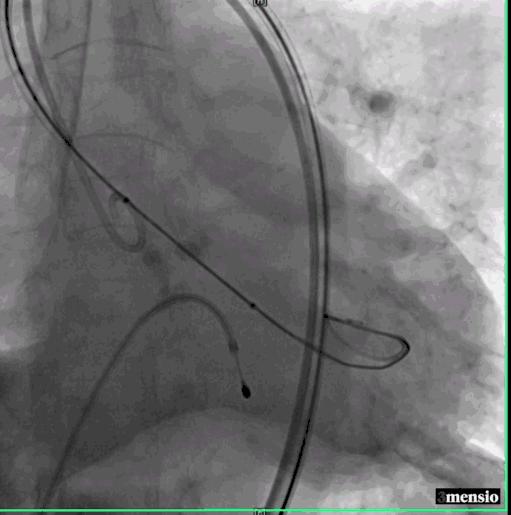

患者穿刺左侧股动脉成功,置入6F血管鞘,沿泥鳅导丝送6F JR4.0造影管至右侧髂总动脉,造影明确右侧股动脉穿刺点,成功穿刺右侧股动脉,植入6F血管鞘,血管鞘内给予肝素3000u。

左侧穿刺股静脉,植入6F血管鞘,预留临时起搏器。追加肝素3000u,右侧预留2把ProGlide缝合器,并更换8F血管鞘。左侧股动脉经泥鳅送6F猪尾导管到升主动脉,行主动脉根部造影示主动脉瓣钙化,重度狭窄。

第一次造影

右侧股动脉鞘经Amplatz Super Stiff导丝引导更换为14F 导引鞘,经右侧股动脉用直头导丝带AL2造影管至升主动脉,在直头导丝引导下成功跨越主动脉瓣。

交换Amplatz Super Stiff导丝,再送猪尾导管至左心室,测量左室压力142/6mmHg,升主动脉压力254/58mmHg,跨瓣压差112mmHg,交换Amplatz Super Stiff导丝至左室,撤出猪尾导管,在临时起搏器控制性降压下用20mm球囊扩张主动脉瓣。